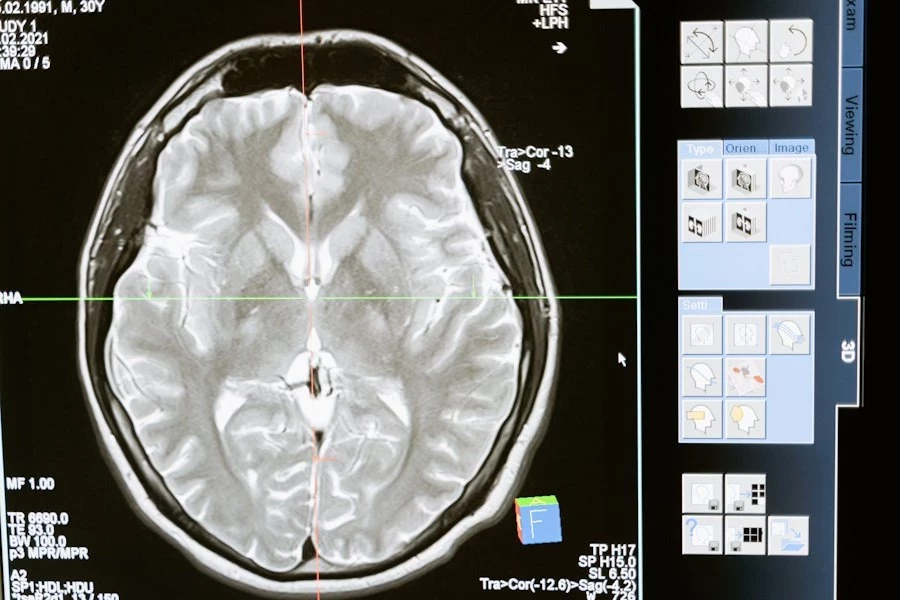

Российские учёные сделали важный шаг в борьбе с одной из самых агрессивных форм рака мозга — глиобластомой. Команда исследователей нашла комбинации молекул-аптамеров, которые значительно снижают способность опухолевых клеток к делению и распространению. Это открытие может привести к созданию новых, более эффективных препаратов против глиомы, сообщает RT.

Глиобластома — это злокачественная опухоль, которая часто оказывается устойчивой к лечению. Препятствия на пути к её терапии включают сложность хирургического удаления, низкую эффективность химиотерапии из-за гематоэнцефалического барьера, а также высокий риск рецидивов.